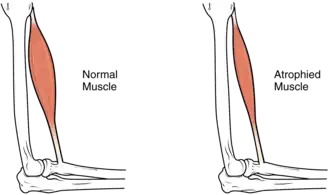

Hypertrophy and atrophy

Hypertrophy is increase in muscle size from an increase in size of individual muscle cells. This usually occurs as a result of exercise.